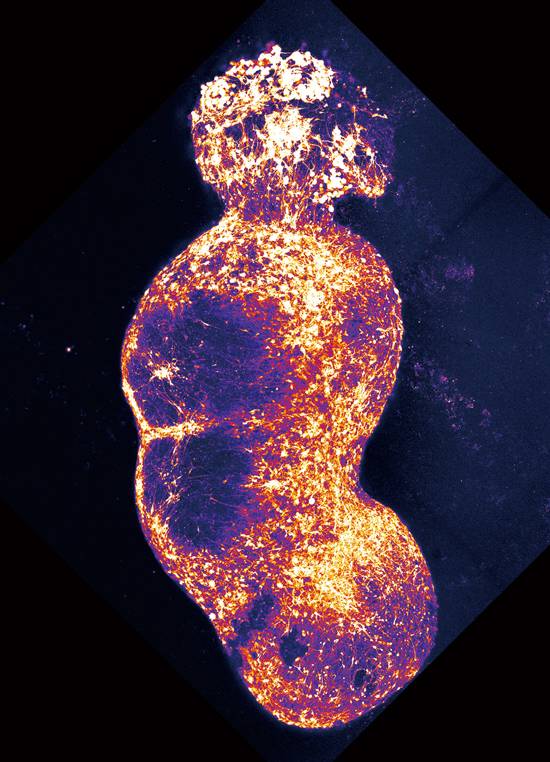

연구진은 iPS세포를 각각 감각신경세포와 척수, 시상, 대뇌피질 세포로 분화시켰다. 이 세포는 3D(입체) 환경에서 오가노이드로 자랐다. 길이는 0.25㎝ 정도였다. 좁쌀만 한 크기다. 100일간 오가노이드를 한곳에 두고 키우자, 신경세포가 서로 연결돼 소시지 모양으로 자랐다. 맨 앞에는 감각 오가노이드가 있고 그 뒤로 척수, 시상, 대뇌피질 오가노이드가 결합됐다.

조립형 미니 장기인 어셈블로이드(as-sembloid)가 탄생한 것이다. 길이는 1.25㎝로 쌀알 두 개 정도였다. 파스카 교수는 “어셈블로이드의 신경세포는 400만 개 정도로, 1700억 개가 있는 뇌에 크게 못 미치는 수치지만, 통증 전달 경로에 관련된 회로를 요약해 놓은 것과 같다”고 말했다.